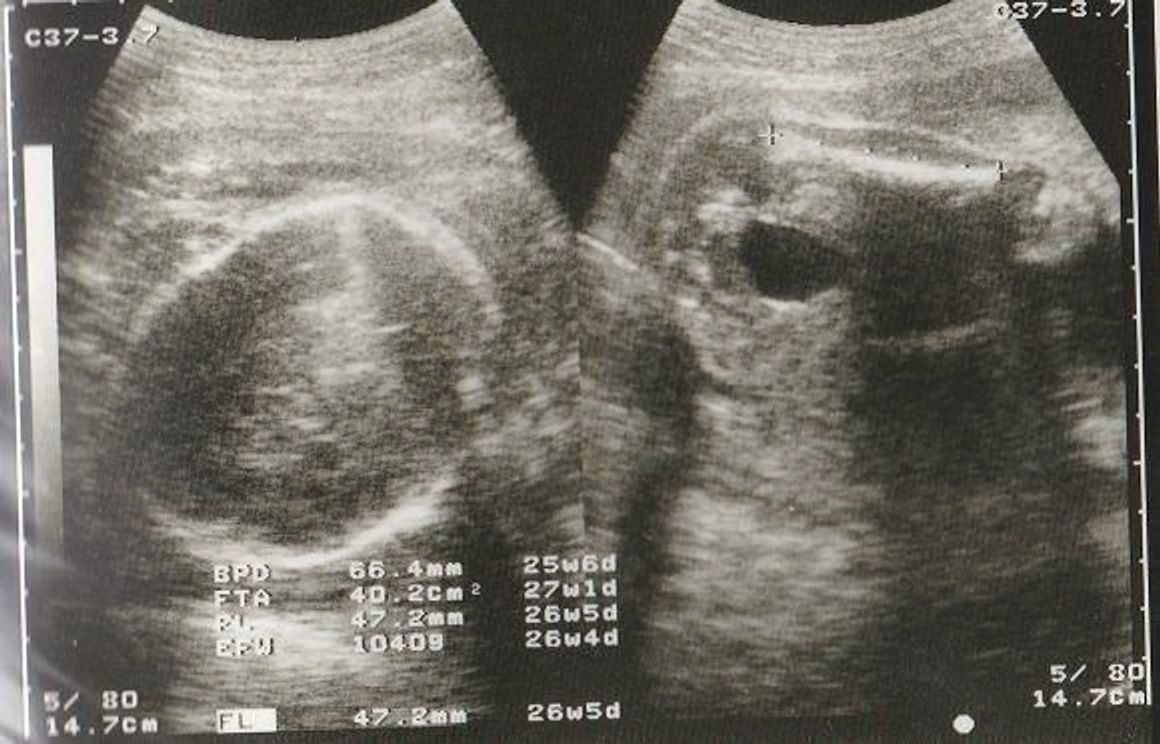

エコー写真の用語:頭部(BPD) BPD:児童大横経(頭の横幅の長さ) GA:エコー測定値から算出した妊娠週数 SD:標準偏差(統計上のばらつき) BPD 599mm GA 24w3d14SD この写真では、頭の横幅の長さが599mm、それは妊娠24週3日目の標準と同じ位で、標準偏差妊娠 性別詳しいかたお願いします 5ヶ月エコーなんですがおちんちんとたまにしかみえないから男の子と数名に言われたんですが三本線あるから女の子ぢゃない?て聞いたらお股から写したやつなら三本線てゆーけ 質問No

今日でW!6ヶ月です!! 妊娠生活も折り返し地点かと思うと、感慨深いです。 そして、今日は月1の診察日でした。 胎動を感じてからは初めての検診だから、 今までみたいに「生きてるかしら?元気かしら?」って不安がないのは 大きな変化だね。女の子エコー写真股 最高 3dエコー 女の子女の子 エコーって、普遍てきな話題かも・・・って、女の子 エコーについては、思ってりしますね! エコー写真。 妊娠七ヶ月 (26週)見て股を閉じていました。 閉じていた少しの隙間から突起物みたいなのが見え 骨盤の男女差や違いを画像を用いて解説します 私たち人間の身体機能の核心である骨盤。 その骨盤は男性と女性で形が違うのをご存知でしょうか。 医療従事者でなければあまり意識することはないかもしれませんが、よくよく考えてみると骨盤に収まっ